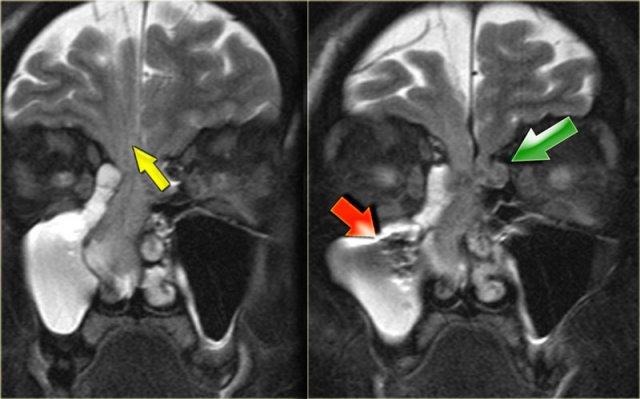

Hình ảnh bên trái của một bệnh nhân bị viêm xoang cấp tính và bệnh lý tế bào khí sàng.

Bệnh nhân nhập viện với triệu chứng nhìn mờ.

Hãy quan sát kỹ các hình ảnh trước, sau đó tiếp tục đọc.

Chú ý dịch trong mỏm yên trước trái.

Dây thần kinh thị giác chạy ở phía trong của nó.

Tiếp tục xem các hình ảnh mặt phẳng coronal.

Chuỗi xung T2W mặt phẳng coronal cho thấy sự giãn rộng của mỏm yên.

Chuỗi xung T1W cho thấy mất tín hiệu mỡ bình thường so với bên phải, và lan rộng vào đỉnh hốc mắt (mũi tên đỏ).

Đây là nang nhầy của mỏm yên trước với tổn thương thứ phát dây thần kinh thị giác.